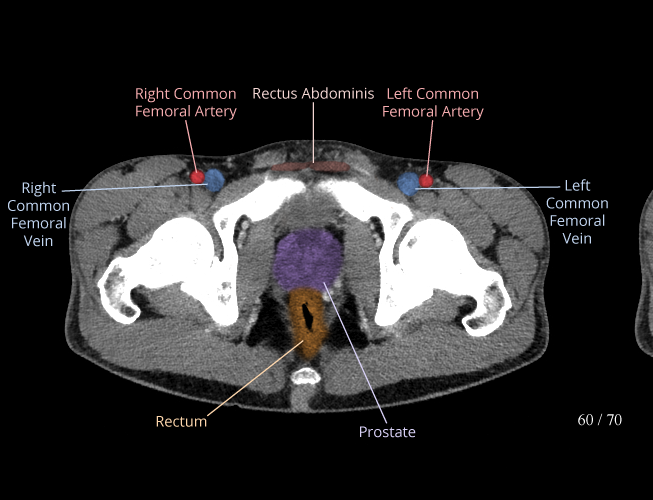

Pelvis

Covers pelvic MRI anatomy.